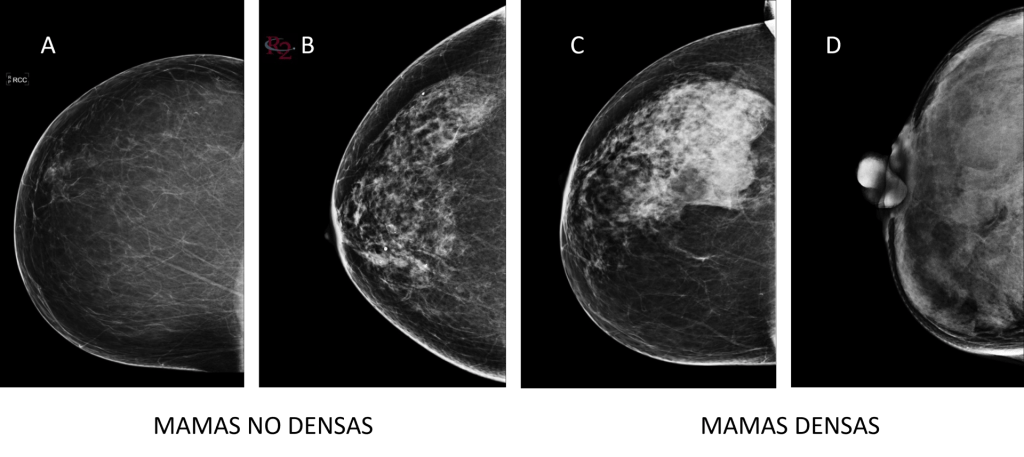

La estimación visual de la mama establece cuatro niveles de densidad:

- A. Las mamas son totalmente grasas.

- B. Hay áreas dispersas de tejido fibro-glandular.

- C. Las mamas son heterogéneamente densas, lo que puede ocultar masas pequeñas.

- D. Las mamas son extremadamente densas, lo que disminuye la sensibilidad de la mamografía.

La distribución de estas categorías en la población en edad de cribado es, aproximadamente, del 10 % con A; 40 % con B; 40 % con C y 10 % con D. Por lo que C y D se considera mama densa.

La mamografía convencional refleja el tejido fibro-glandular con áreas más blancas o brillantes, mientras que la grasa aparece representada de forma más oscura.